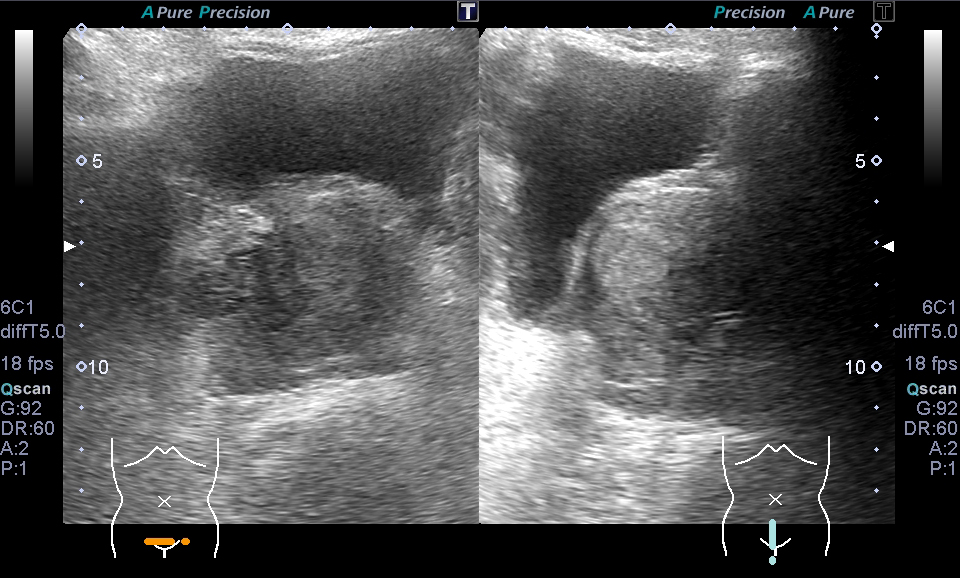

超音波(エコー) 診断画像

- 内頸動脈狭窄

- 転移性肝がん

- 胆嚢ポリープ

- 胆石

- 大腸がん

- 前立腺肥大・前立腺がん

- 腎細胞がん

- 子宮筋腫

- 心エコー(大動脈弁・僧帽弁閉鎖不全症)

- 胃がん